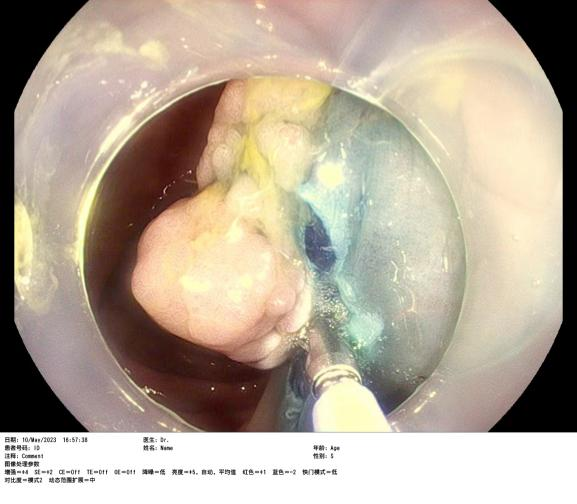

患者賴女士因下腹部疼痛不适半月,在惠州六院行腸鏡檢查時(shí)發(fā)現橫結腸腫物,腫物大小約2.8cmx2.0cm,表面(miàn)充血,于是入院完善采血、心電圖、胸片、全腹部增強CT等一系列檢查,增強CT結果提示腫物未見腸管外浸潤生長(cháng),經(jīng)評估該患者有手術指征,在與患者及家屬充分溝通後(hòu),由消化内科蘇連明副主任醫師爲患者行内鏡下結腸黏膜剝離術(ESD),手術非常順利,術後(hòu)病理及免疫組合明确診斷爲高級别上皮内瘤變——俗稱早期結腸癌。